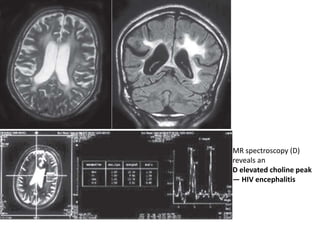

Imaging Findings

• MRS shows low NAA a finding that reflects

lower number of neurons (due to their death)

and neuronal dysfunction. Elevated choline

peak reflect the presence of gliosis, microglial,

foamy macrophages and lymphocytes.

Elevated myoinositol (MI) occurs early in

infection and is a reflection of gliosis

MR spectroscopy (D)

reveals an

D elevated choline peak

— HIV encephalitis